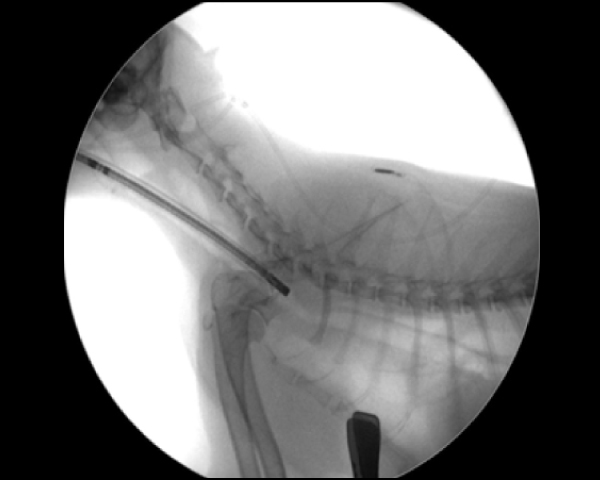

Cアームを用いたバルーン拡張術

拡張後の鼻咽頭部